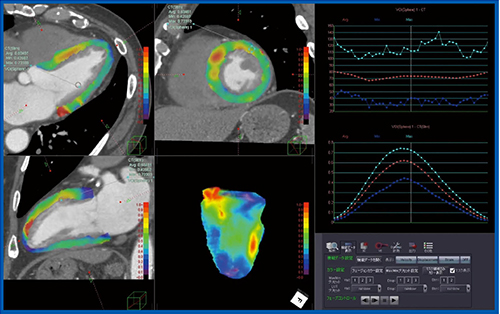

PhyZiodynamicsの画像補完技術を使った、新しい心機能解析ソフトウエアである“CTストレイン解析”について紹介する。CTストレイン解析は、4Dモーション解析による“Maximum Principal Strain”を算出するソフトウエアである。PhyZiodynamicsによるボクセルのトラッキングなどの情報を利用して、組織の主歪みの中で最大のものを求めることが可能である。これまで超音波やMRIでは、2Dの解析から心筋の内膜重心方向に向かうRadial Strain、回転方向のCircumferential Strainなどを計測していたが、PhyZiodynamicsでは4Dで心筋全体の評価が可能となり、主方向における最大の歪みを求めたMaximum Principal Strainという指標を出すことができる。

実際の計測では、心筋の任意の断面で解析して4D画像の作成も可能で、VOIを置いた領域のストレインカーブも表示できる。これによって心筋の局所のストレイン解析が可能になると期待される(図7)。

図7 CTストレイン解析